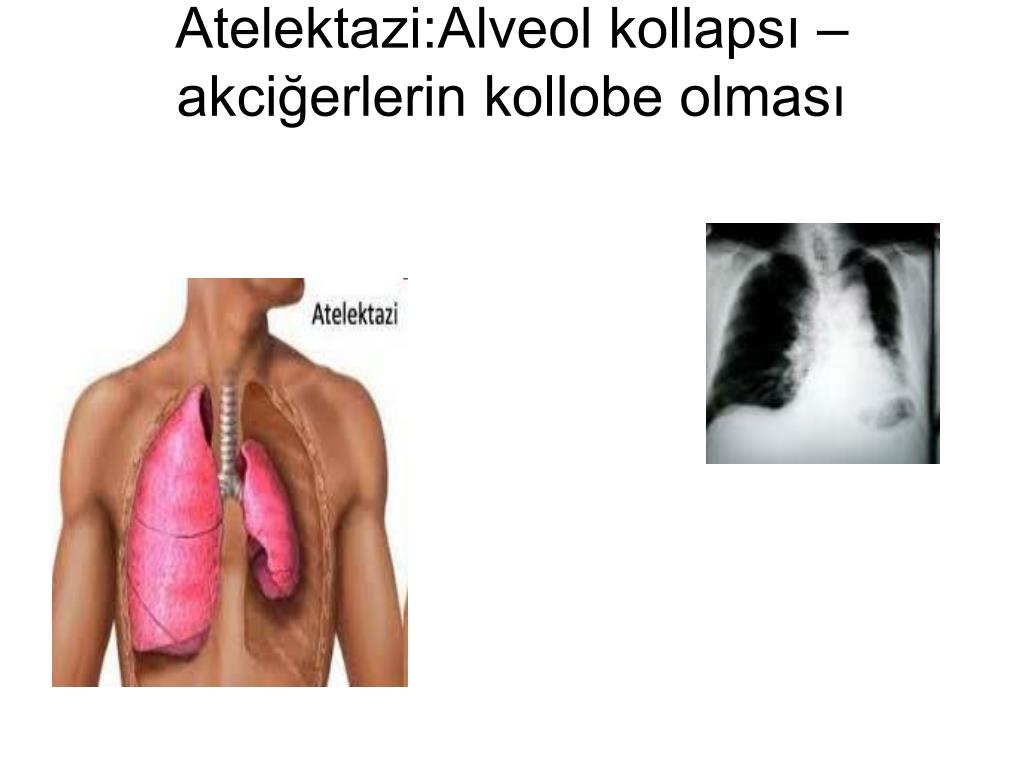

Схемы дыхания: Пневмоторакс на изображениях